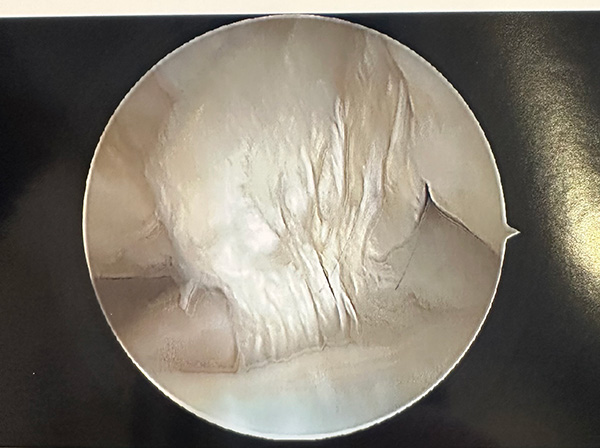

One of the compelling aspects of Katherine’s treatment involved a cartilage transplant procedure. Her knee had several defects in the joint surface where cartilage and bone broke off. This required finding a deceased donor with a bone size and curvature like hers. Katherine’s cartilage donor needed to be a child with healthy and fresh cartilage, versus an active adult.

The procedure involved drilling into the defective joint, removing 7-10 millimeters of bone under the cartilage, taking the same size from the donated tissue, and inserting it in place of the removed bone. Over the next six to eight weeks, the patient’s bone grows into the transplanted bone. Meeks said this advanced procedure has an impressive 85%-90% lifespan at 10 years.